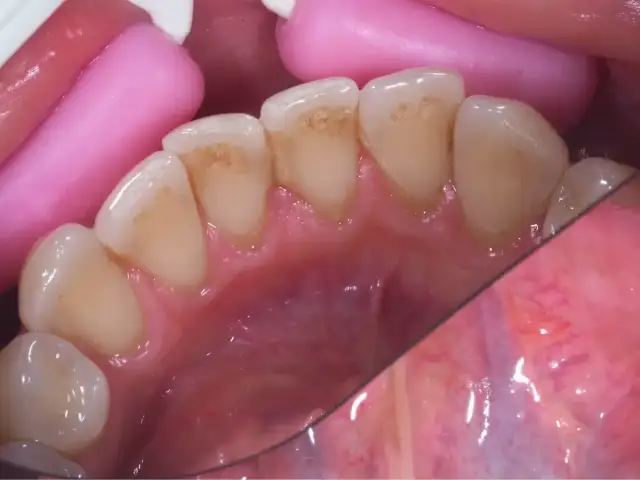

Dowiedz się, jak wygląda kamień na zębach, jakie są jego objawy oraz skutki zdrowotne. Zadbaj o zdrowie jamy ustnej i unikaj problemów!